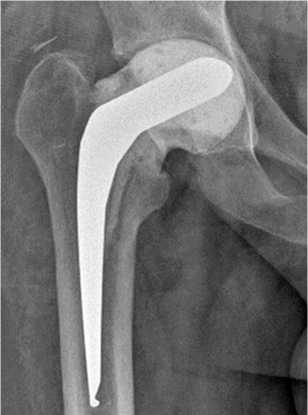

10.10.2023 произведена операция в объеме: удаление артикулирующего спейсера, тотальное бесце-ментное эндопротезирование правого тазобедренного сустава эндопротезом «ЭСИ» (рис. 7).

Рис. 7. Рентгенограмма правого тазобедренного сустава пациента К. в первые сутки после операции тотального бесцементного эндопротезирования правого тазобедренного сустава эндопротезом «ЭСИ»

Через 12 мес. после операции тотального бесцементного эндопротезирования правого тазобедренного сустава эндопротезом "ЭСИ" функциональные показатели сустава по шкале HHS — 91, по шкале WOMAC — 11, выраженность болевого синдрома по шкале ВАШ — 0 баллов. Рентгенограмма представлена на рис. 9.

Рис. 9. Рентгенограмма правого тазобедренного сустава пациента К. через 12 мес. после операции тотального эндопротезирования левого тазобедренного сустава